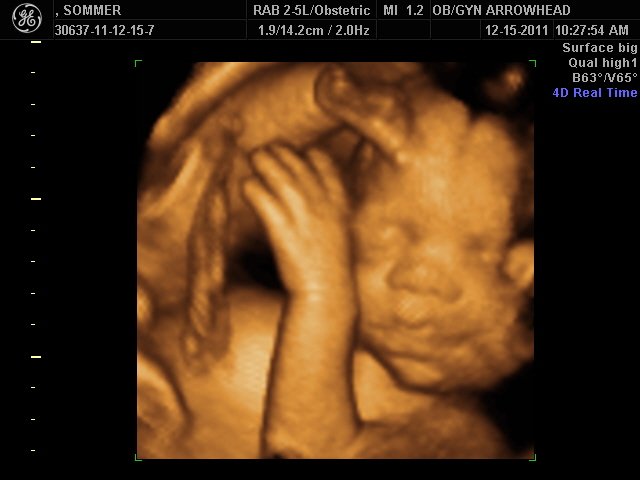

We offer complimentary 3D/4D Ultrasounds to all our OB patients around 30 weeks! The following photos are some examples of our work, shown with permission from our patients.